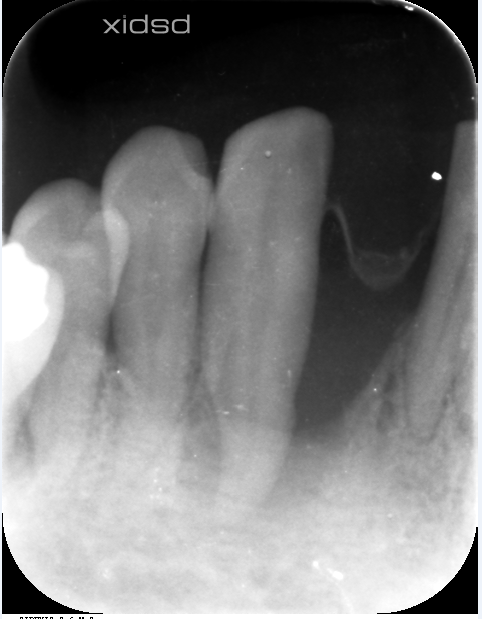

レントゲン

根尖まで骨がなく。。。。グラグラでした。

昨日の検査で数値が健康に戻りました!!